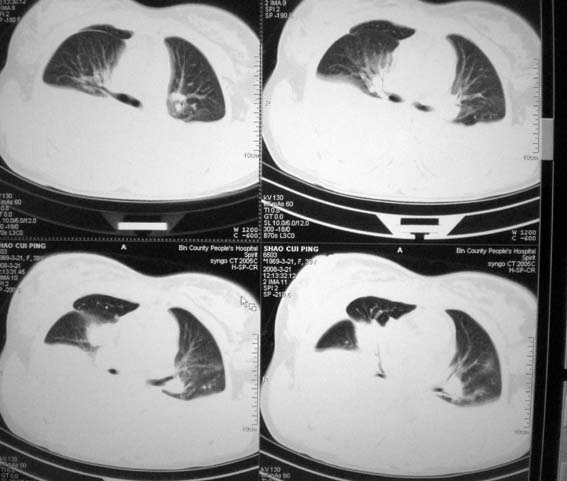

以下是引用zsl6918在2008-3-21 21:41:00的发言:[br]胸腔积液,心包积液,明确性质有难度。常规思路考虑结核性,建议抽液化验明确。

以下是引用卜一在2008-3-22 1:48:00的发言:[br][br] [br] 大量胸腔积液伴肺组织膨胀不全+心包积液。建议行纤支镜! [br] [br]

以下是引用随光逐影在2008-3-21 23:13:00的发言:[br]1)右肺中叶及左肺上叶舌段感染性病变。2)右肺中叶周围型肺癌待排。3)双侧胸腔积液并双下肺部分肺组织膨胀不全。4)心包积液。

以下是引用拾荒者在2008-3-22 21:21:00的发言:[br]胸腔积液、心包积液,双下肺膨胀不全,建议穿刺细胞学检查或抽液后进一步ct检查。